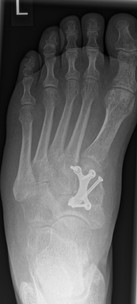

3.- April 2017: Schraubenbruch

Im Rahmen einer Verlaufskontrolle zeigte sich ein Schraubenbruch als Zeichen einer fehlenden Durchbauung der Arthrodese.